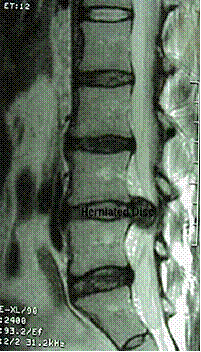

¿Qué es la hernia discal?

La hernia discal es una condición en la cual una parte de la porción central gelatinosa de un disco intervertebral (el núcleo pulposo), o su totalidad, es expulsada a través de una parte debilitada del disco. Esto se traduce en dolor de espalda y dolor en las piernas (hernia lumbar) o dolor en el cuello y dolor en los brazos (hernia cervical) debido a la irritación de un nervio.

HERNIAS DEL NUCLEO PULPOSO (HNP)